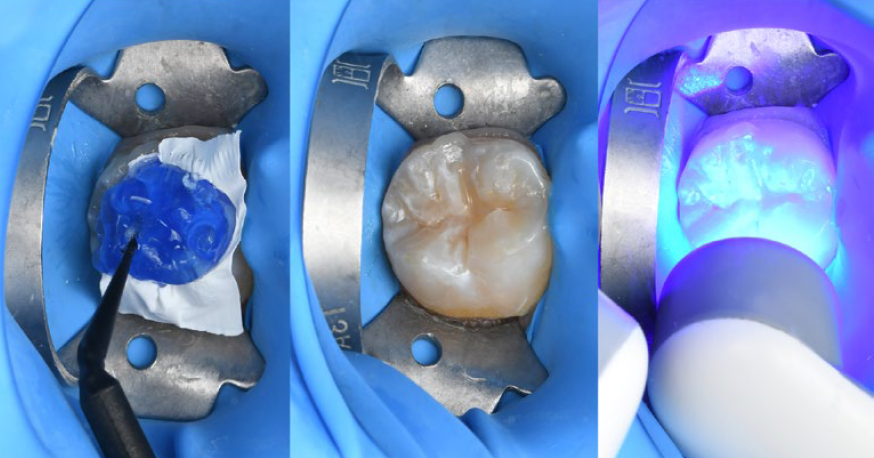

A possible clinical protocol is illustrated in Figures 2 to 5: After caries excavation and tooth preparation, sectional matrices, wedges and rings were placed to allow for simultaneous treatment of the mesial and occlusal cavities. Following etching and application of the universal adhesive CLEARFIL™ Universal Bond Quick (Kuraray Noritake Dental Inc.), the cavities were restored with CLEARFIL MAJESTY™ ES Flow Super Low A1 shade and CLEARFIL MAJESTY™ ES-2 Universal in shade U. The distal cavity of the first molar was filled in the last step of the free-hand modeling procedure. In order to restore the occlusal surfaces in their original vertical dimension, every second tooth was isolated with a rubber dam and the exposed molar etched (total-etch technique with phosphoric acid (K-ETCHANT Syringe, Kuraray Noritake Dental Inc.). The alternating index was positioned with some pressure and the flowable composite (CLEARFIL MAJESTY™ ES Flow Super Low) injected. Once light curing was completed, the index was removed and excess chipped off followed by finishing and polishing the restoration before repeating the procedure for the adjacent molar.

Fig. 4: Restoration of two molars: Re-establishing the occlusion with the aid of the flowable injection technique.

Fig. 5: Alternating approach: Restoration of the second molar by injecting flowable composite.